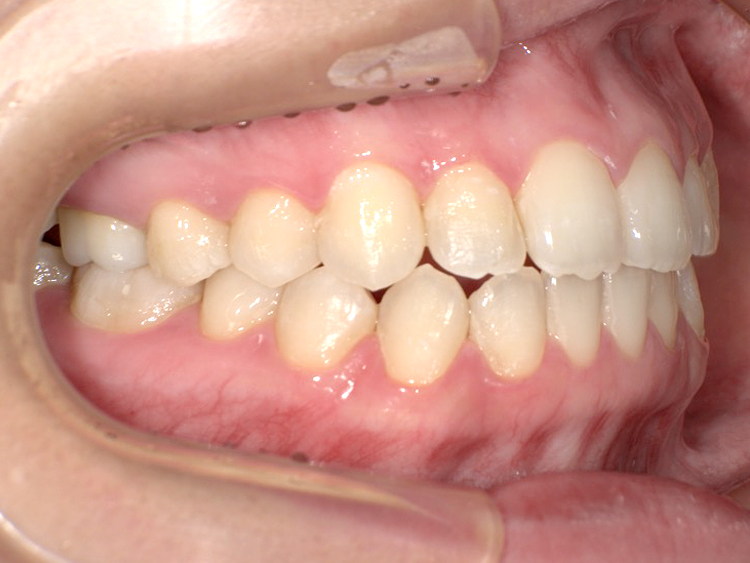

症例6

Before

After

| 主訴 | 噛み合わせが気になる |

|---|---|

| 年齢 | --- |

| 治療 期間 |

約2年11ヶ月 |

| 治療 内容 |

インビザラインコンプリヘンシブ 右上6番・左上6番ALLセラミッククラウン |

| 治療費 | ¥1,116,000(税込)/調整料含む |

| 治療のリスク | 歯を動かすことで、歯茎が下がるリスクある。 矯正終了後は、リテーナーを使用し、後戻りを防ぐ必要がある。 |